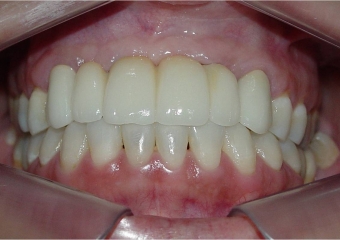

Imagem final

Próteses fixas em porcelana instaladas

Sorriso final, do caso terminado em Novembro de 2013